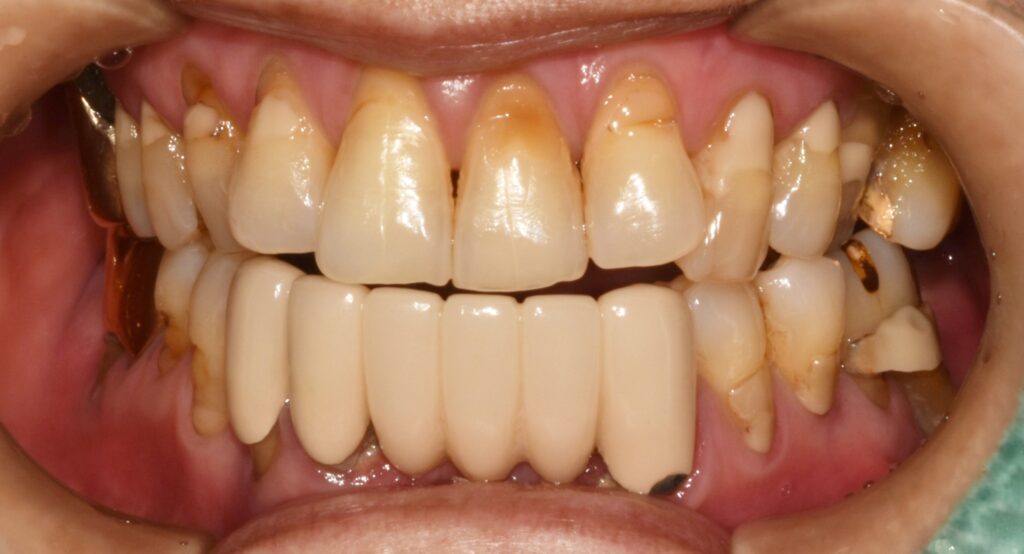

초진 상태

처음 오셨을 때의 구강 내 상태입니다.

대부분의 어금니가 심하게 흔들리고, 잇몸에서는 고름이 나오는 부위도 관찰됩니다.

어금니는 씹는 힘을 담당하는 중요한 치아이기 때문에 어금니가 무너지면 위아래 치아가 서로 안정적으로 맞물리는 교합관계도 함께 무너지게 됩니다.